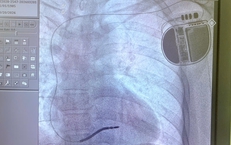

Cứu sống bệnh nhân vỡ động mạch chủ bụng bằng Stent graft

Y tế - 10/10/2025 14:54SKĐS - Vừa qua, các bác sĩ Bệnh viện Hữu Nghị đã cứu sống một bệnh nhân 76 tuổi bị vỡ túi phình kích thước gần 8cm (động mạch chủ) bằng kỹ thuật can thiệp nội mạch hiện đại, đây là một tình trạng cấp cứu y khoa có tỷ lệ tử vong cao.